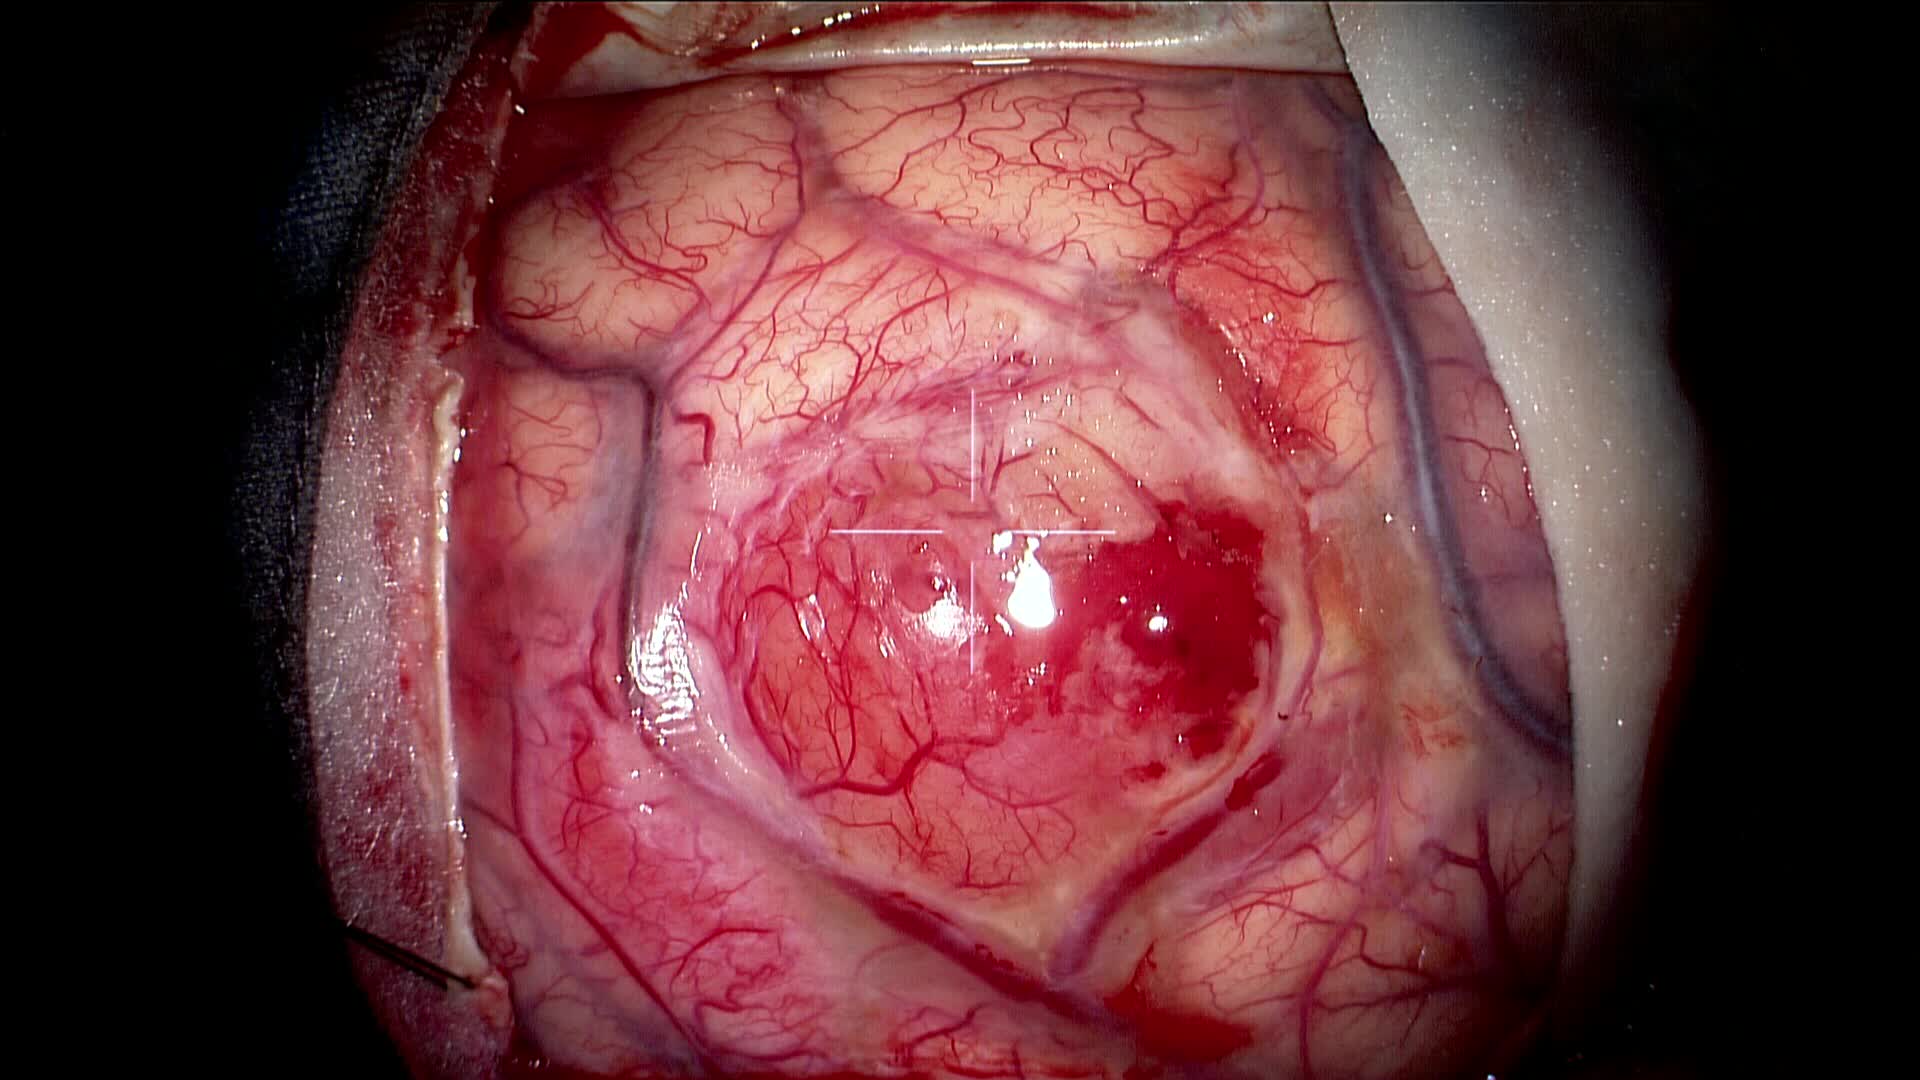

Resezione microchirurgica di tumore cerebrale (glioma alto grado cortico-sottocorticale) frontale dx